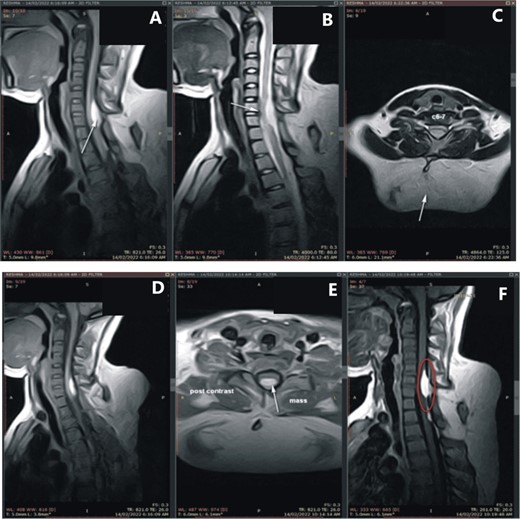

A magnetic resonance imaging (MRI) scan of the neck, conducted with and without contrast following standard protocols, displayed a large, poorly encapsulated fat signal mass in the inferior neck and superior dorsal region, with intraspinal epidural extension at the C6-C7 vertebral level, protruding into the spinal canal and positioned posteriorly opposite to the C6 and C7 vertebral bodies, inducing moderate spinal compression of the cervical cord displacing anteriorly. A bony structure was observed connecting the spinous process at the C6 vertebral body to the T3 vertebral body. The prominent characteristics are indicative of a congenital fat-containing mass with intraspinal epidural involvement. The differential diagnosis encompasses, but is not restricted to, spinal dysraphism associated with lipoma, teratoma, or a dermoid mass (Fig. 2).

(A) MRI of the cervical and dorsal spine; (C) a large, poorly encapsulated fat signal mass in the inferior neck and superior dorsal region (white arrow), and (B, D) an intraspinal epidural extension at the C6-C7 vertebral level, protruding into the spinal canal and positioned posteriorly opposite to the C6 and C7 vertebral bodies (white arrows), and (A, F) a bony structure connecting the spinous process at the C6 vertebral body to the T3 vertebral body (white arrow and red circle).